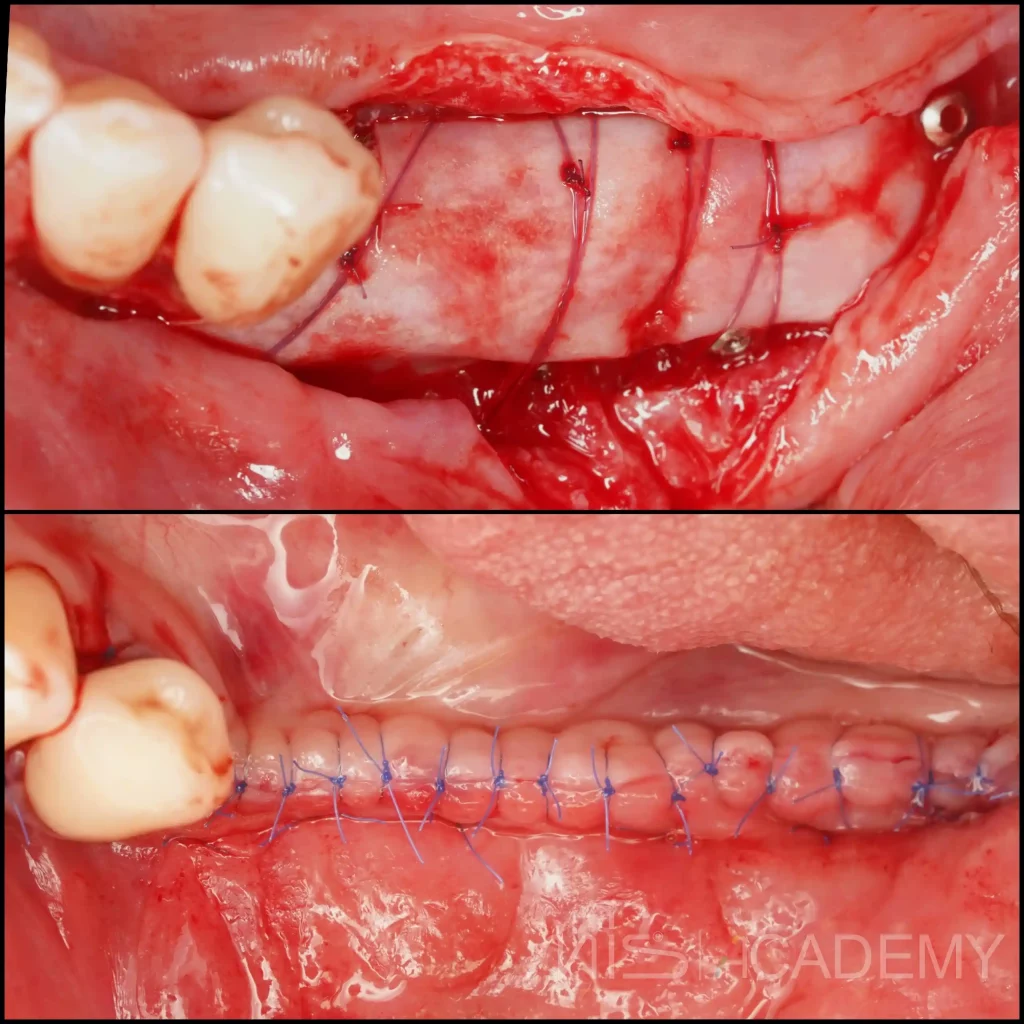

Вертикальный костный дефект

— Фиксация титановых пластин для создания барьера

— Ауто + ксено

— Раскрытие через 7 месяцев